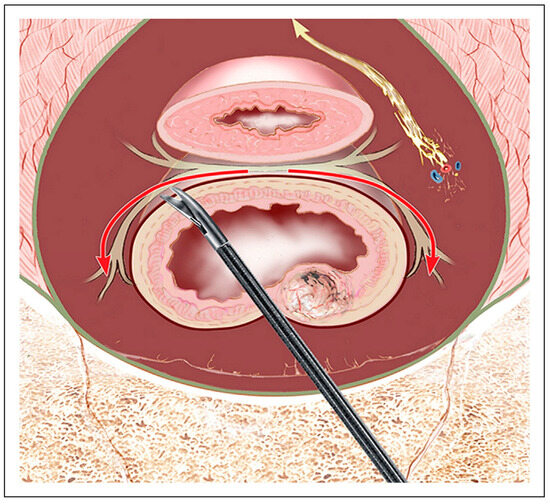

| Near-Infrared Fluorescence (NIR) | Uses ICG or targeted agents for real-time visualization | Improves intraoperative nerve visibility | [41,53] |

- Jin, H.; Zheng, L.; Lu, L.; Cui, M. Near-infrared intraoperative imaging of pelvic autonomic nerves: A pilot study. Surg. Endosc. 2022, 36, 2349–2356. [Google Scholar] [CrossRef] [PubMed]

| Lateral Dissection | Dissect on the outer surface of the visceral/mesorectal fascia (fascia propria); clip/divide nervi recti and middle rectal vessels at mesorectal entry (≈4 & 8 o’clock); avoid behind-parietal-fascia skiving or skeletonizing ureter/iliac vessels. For the final release adjacent to the IHP, prefer sharp (cold) dissection over energy. | IHP, PSN; limits traction/thermal injury and lets plexus recoil laterally. | [26,44,45] |

| Anterior Dissection | Dissect behind Denonvilliers’ fascia or septum | Cavernous nerves, neurovascular bundles | [26,54] |